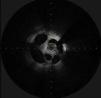

Um doente de 67 anos com cardiopatia isquémica e fração de ejeção gravemente comprometida foi submetido a coronariografia, no contexto de um enfarte agudo do miocárdio sem supradesnivelamento de ST. A coronariografia revelou uma lesão na artéria coronária descendente anterior proximal (Vídeo 1). A aparência angiográfica da lesão não permitia esclarecer inequivocamente a sua natureza, tendo‐se colocado a hipótese de dissecção complexa versus trombo recanalizado. Nesse sentido, realizou‐se OCT (Figura 1 e Vídeo 2). A invulgar imagem obtida permitiu confirmar a presença de múltiplos lúmenes na artéria descendente anterior, aparentemente no contexto de recanalização de trombo, pelo que se procedeu à realização de angioplastia da descendente anterior com colocação de stent com fármaco, com excelente resultado final (Vídeos 3 e 4).

A recanalização de trombos pode, por vezes, originar imagens angiográficas de grande complexidade, sugerindo inclusivamente etiologias que colocam maior desafio técnico, como dissecções complexas. A realização de métodos de imagem intracoronários, como OCT, permitem clarificar a natureza destas lesões e permitir o tratamento adequado, evitando ao mesmo tempo o desencadear de abordagens técnicas mais complexas com potencial iatrogenia.